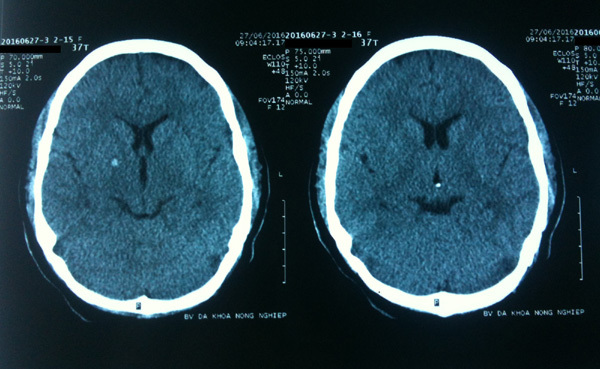

Ngay lập tức, bệnh nhân được thở oxy, truyền dịch, cố định cột sống cổ. Tiến hành chụp cắt lớp vi tính sọ não, các bác sĩ phát hiện bệnh nhân chảy máu não nhỏ vùng bao trong phải và não thất III nên được chuyển tiếp Bệnh viện Bạch Mai để tiếp tục điều trị và theo dõi.

![]() |

| Hình ảnh xuất huyết não trên phim chụp cắt lớp. Ảnh: BSCC |